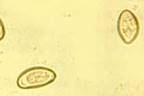

Для Opisthorchis felineus характерно продолговатое тело, заметно суживающиеся к переднему концу. Длину 8-13 ширина 1,2-2,5 мм. Специфический признак – наличие 2 – лопастных семенников расположенные наискось в задней части тела. Между ними проходит экскреторный канал S-образной формы. Петли матки расположены впереди семенников. Яйца мелкие 0,01-0,02 х 0,002-0,003 мм бледножелтого цвета, с нежной двухконтурной оболочкой, крышечкой на одном и бугорочном на противоположенном полюсе. Яйца при выходе наружу уже инвазионны т.к. содержат мирацидии.

Яйца Opisthorchis filineus

Основным является гельминтокопрологическое исследование. Яйца мелкие, размером 0,02-0,03*0,01-0,02 мм, желтоватые, с крышечкой и утолщением скорлупы на одном из концов. Можно использовать и иммунобиологические реакции. Через 10-20 мин после введения аллергена (0,1 мл внутрикожно в наружную поверхность ушной раковины) у заражённых животных образуется хорошо видимая и легко прощупываемая папула, 1,5-2 см в диаметре.